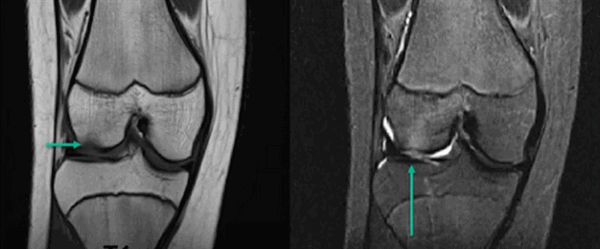

Основы. КСС. Коленный сустав. Травма. Патология. +

В связи с бурным развитием в последние годы современных средств медицинской визуализации - магнитно-резонансной томографии (МРТ), рентгеновской компьютерной томографии и расширением возможностей ультразвуковой диагностики - роль классической рентгенологии в диагностике травматических повреждений суставов, в частности коленного, иногда незаслуженно недооценивается.

В то же время рентгенография остается наиболее распространённым объективным методом диагностики и контроля эффективности лечения повреждений коленного сустава. Принято считать, что при травмах коленного сустава чувствительность рентгенографии не превышает 5 - 7%, поскольку она позволяет диагностировать только костные изменения.

Однако, анатомические и биомеханические особенности коленного сустава изначально предопределяют значительно более частые повреждения не костных структур, а связочно-менискового комплекса (СМК). Поэтому, высокий процент первичных диагностических ошибок при повреждениях СМК объясняется тем, что при анализе рентгенограмм основное внимание уделяется только наличию или отсутствию костных изменений. В результате, как свидетельствуют наши наблюдения, среднее время от момента получения травмы (и, соответственно, проведения первичной рентгенографии) до установления правильного диагноза составляет 6 месяцев и более. Вместе с тем, существуют многочисленные функциональные пробы и укладки при рентгенографии коленного сустава, которые позволяют анализировать и на основании определённых признаков предполагать с большой долей вероятности наличие повреждений СМК. С учетом выявленных изменений обследование при необходимости может быть дополнено более сложными методами лучевой визуализации.

Излагаемое ниже основано на опыте сопоставления рентгенограмм 150 больных с травмой коленного сустава без явных изменений костных структур в сопоставлении с данными КТ и МРТ этих же больных, а в 57 случаях - и артроскопии. Дополнительные исследования были выполнены этим пациентам после рентгенографии ввиду сохранения болевого синдрома и наличия клинических признаков повреждения внутренних структур сустава, но, как правило, в отдаленные сроки после травмы.